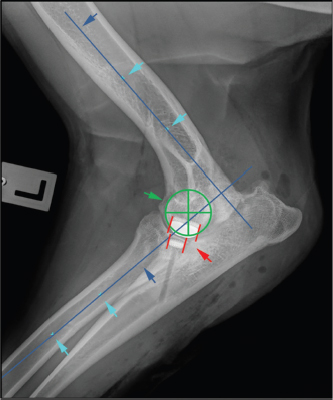

Fig. 3. Determination of long bone axis as well as joint rotation center for measurement of cranio-caudal humero-ulnar implant overlap turquoise arrows: midpoints between cortices at 50% and 30% of the humeral and radial bone length; blue arrows: longitudinal bone axis of humerus and radius; green cross: center of elbow joint rotation, identical with center of humeral condyle; red lines: cranial and caudal edge of the humeral and ulnar implants.

Cranio-caudal overlap of both implants was measured on ML views (Figs. 3 and 4).

First, the humeral longitudinal axis was drawn, as a line connecting the midpoints between both humeral cortices at 50% and distal 30% of its length. The radial longitudinal axis was determined by applying the same principle. A goniometer template was then positioned with each arm parallel to the respective longitudinal axis with the center of rotation at the center of the humeral condyle. Cranial and caudal edges of the implants were then marked on the template (Fig. 3). While the humeral arm of the template remained fixed, the radial arm with marked UImpl edges was first brought into full extension, positioning the ulnar implant caudal to the humeral one and then gradually flexed back to full flexion in order to mimic the full range of elbow motion. Extension angles for six elbow positions were recorded (Fig. 4):

1. Extension angle with no overlap between UImpl and HImpl, with the HImpl just cranial to the ulnar implant (Fig. 4A).

2. Extension angle with 50% UImpl overlap (Fig. 4B).

3. Extension angle with the caudal part of the HImpl overlapping 100% of the UImpl (Fig. 4C).

4. Extension angle with the cranial part of the HImpl overlapping the whole UImpl (Fig. 4D).

5. Extension angle with 50% UImpl coverage (Fig. 4E)

6. Extension angle with no overlap between UImpl and HImpl, with the HImpl just caudal to the ulnar implant (Fig. 4F).

The difference between the largest and the smallest extension angle measured represents the range of elbow motion with implant overlap and is termed the implant contact phase span (ICPS). In cases with multiple ulnar implants, these measurements were repeated, with the caudal border of the most caudal UImpl and the cranial border of the most cranial UImpl set as reference.